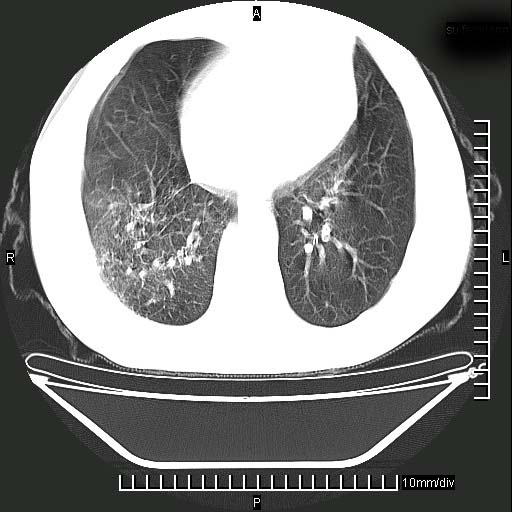

标题: CT24043:胸部增强:男性,60岁

既往肺结核,近10几天,咳嗽,咳痰,右侧胸痛,疼痛较明显,右上肺斑块考虑结核灶胸膜粘连,增强,可惜动脉期没有定好,未见强化,可延迟4分后又见较明显强化,中心见低密度影,如果说结核是边缘强化,可这个灶强化的面积挺大的,让人很挠头。

动脉期

1)两肺继发性肺结核。2)右侧胸膜增厚+少量胸腔积液。